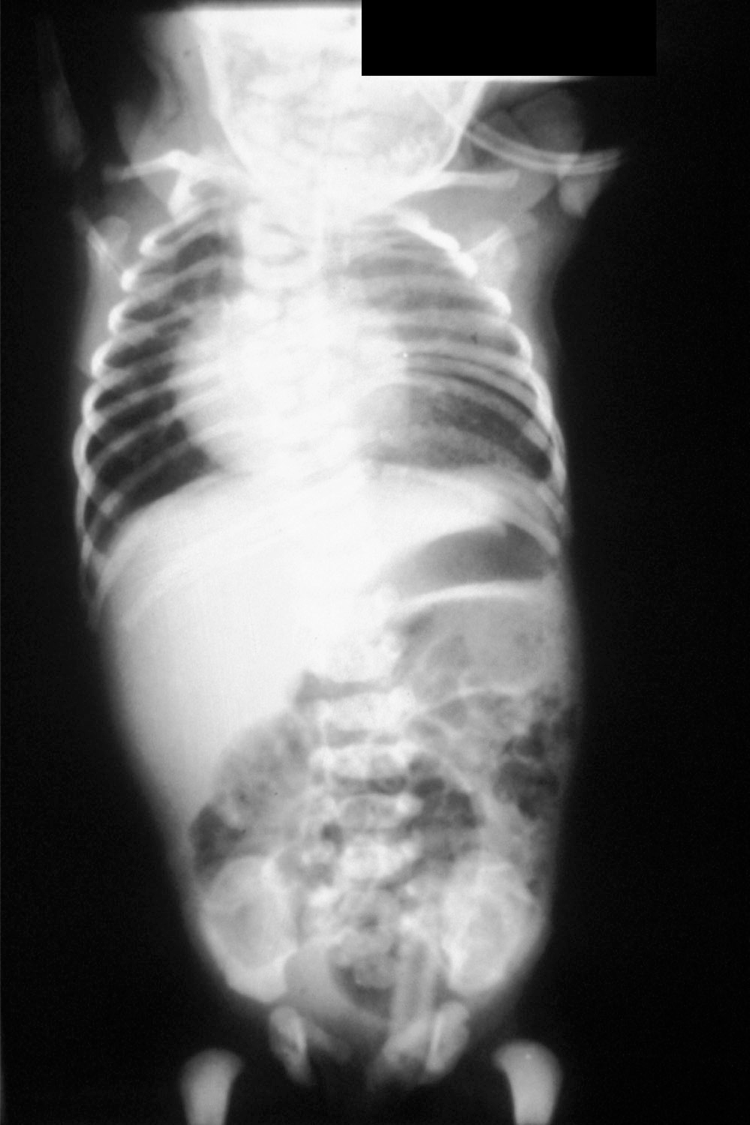

what syndrome is shown here?

Turners is when you have an X chromosome but no Y – 45X

what are the features of Turner syndrome 45,X?